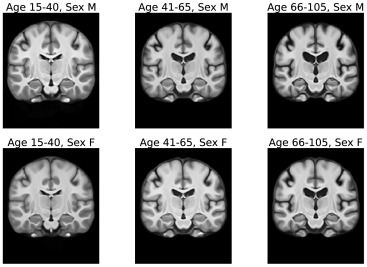

图18我们的配准基线中使用的ANTs-Frag-no-Seg迭代模板。这些模板是通过对按年龄和性别划分的六个不同人群亚组应用ANTs SyGN算法构建的。每个组有100名受试者。

图20使用Aladdin对人群进行分箱后学习到的Aladdin-Frag模板。这些模板是针对每个人群亚组(按年龄和性别划分)使用一个模型学习的。